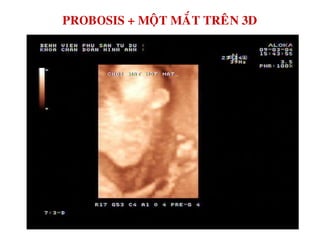

PROBOSIS + MOÄT MAÉT

PROBOSIS + MOÄT MAÉT TREÂN 3D

MOÄT MAÉT